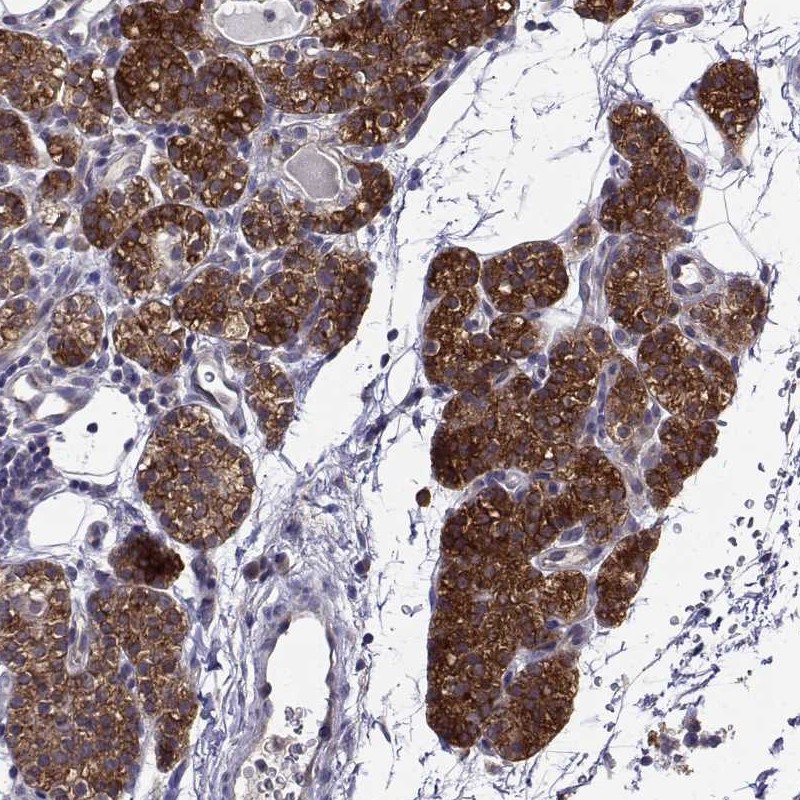

Immunohistochemistry analysis in human parathyroid gland and liver tissues using Anti-STXBP5 antibody. Corresponding STXBP5 RNA-seq data are presented for the same tissues.